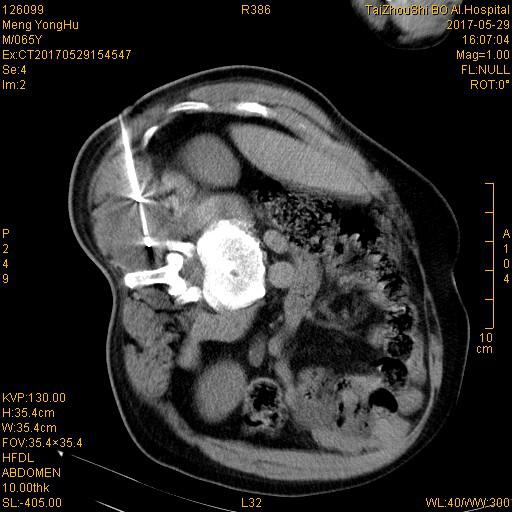

氩氦刀冷冻中定位